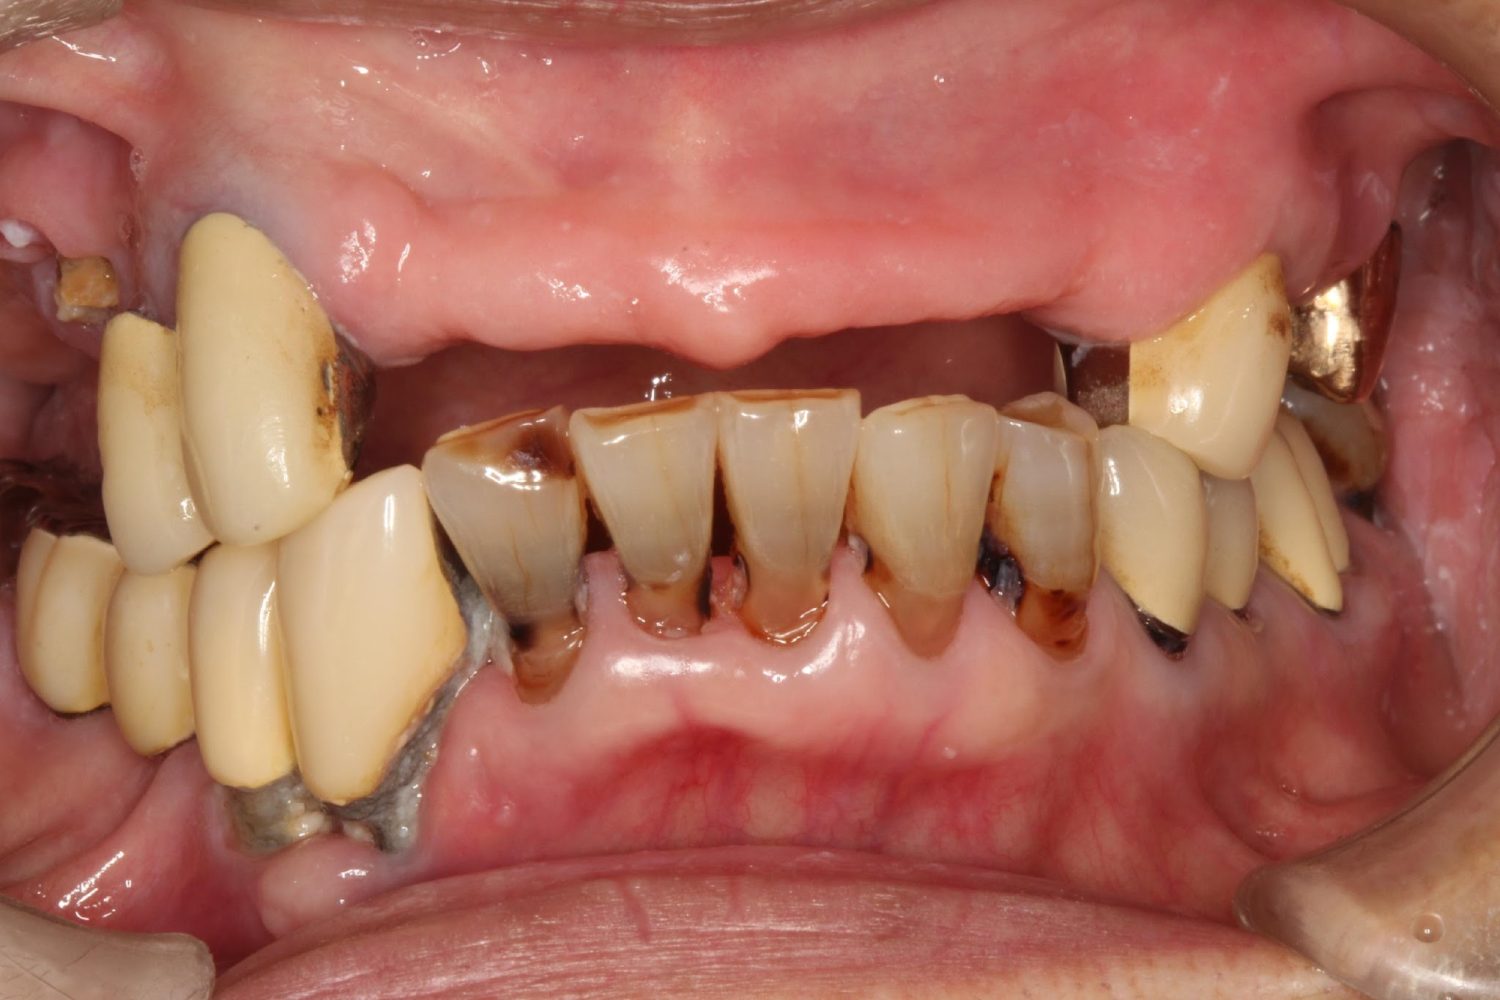

インプラント治療の症例紹介⑤

Before

After

主訴

歯肉腫脹、咬めるようにしたい

治療内容

重度歯周病により全ての残存歯保存不可能な状態。上下顎ボーンアンカードブリッジによる咬合再構成。

治療費

12,621,400円(税込)

治療期間

22ヶ月

通院回数

28回

想定されたリスク

※上部構造の形態が複雑になるため清掃が難しくなる、インプラント周囲炎の恐れがありました。

濱 仁隆先生

浜歯科

上顎8本下顎7本のインプラント体埋入によるボーンアンカードブリッジ。